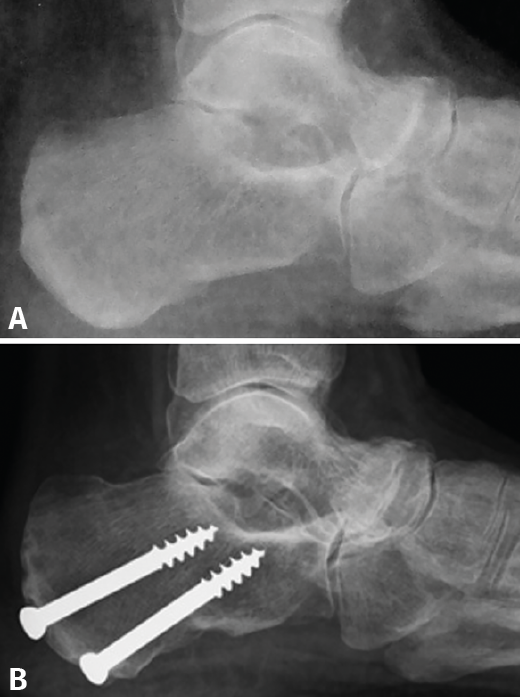

Figura 3. Los cambios radiológicos en la proyección lateral del pie son evidentes después de la cirugía valguizante del retropié. A: artropatía talonavicular en el preoperatorio; B: un año después de la cirugía la articulación muestra un aspecto mejorado por la traslación medial del astrágalo.